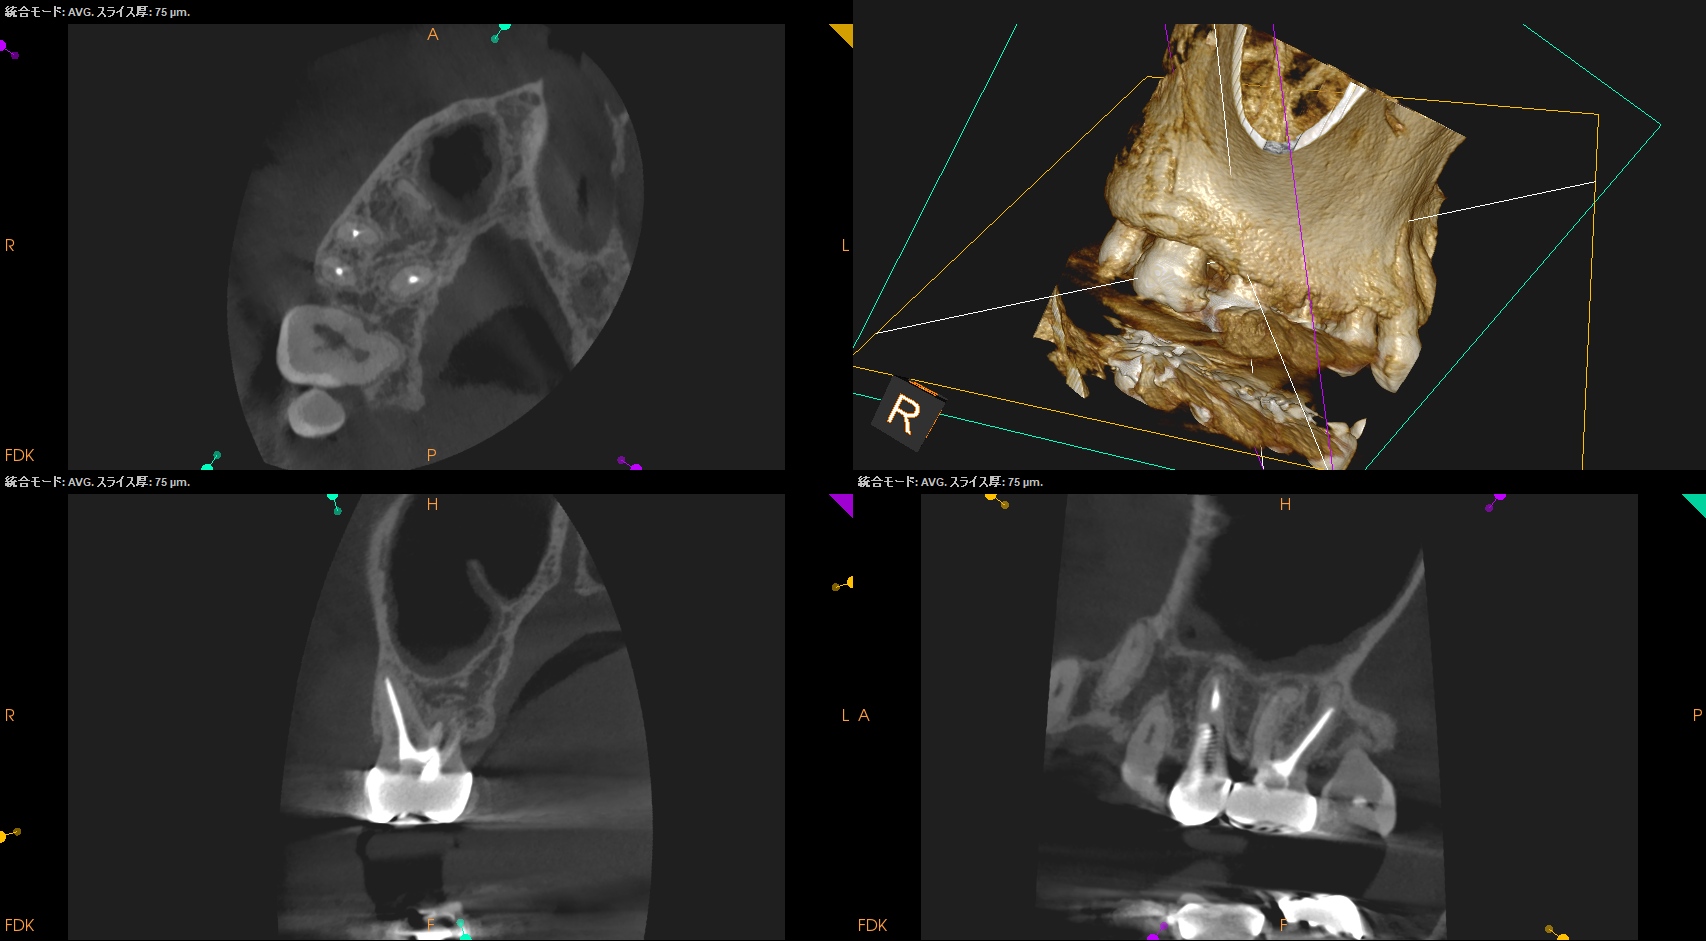

CBCT(2025.9.1)

#3

#4

B

P

#4はP根管が未着手だ。